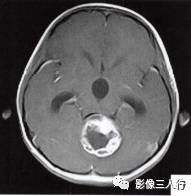

(二)影像所见

头颅MRI扫描示:小脑上蚓部见团块状异常信号影,边缘清楚,大小约4.5cm×3.5cm×3.7cm,T1WI(图B)等信号,中心可见更低信号,T2WI(图A)呈髙信号,水抑制(图C) 等信号,中心呈更低信号,周边可见轻度高信号水肿区。增强后(图D〜F)病灶可见明显环形强化,壁较厚,内壁欠光滑,邻近小脑及第四脑室受压,第三脑室、双侧脑室扩张积水。

诊断:小脑上蚓部占位,考虑肿瘤性病变,以毛细胞型星形细胞瘤可能性大。